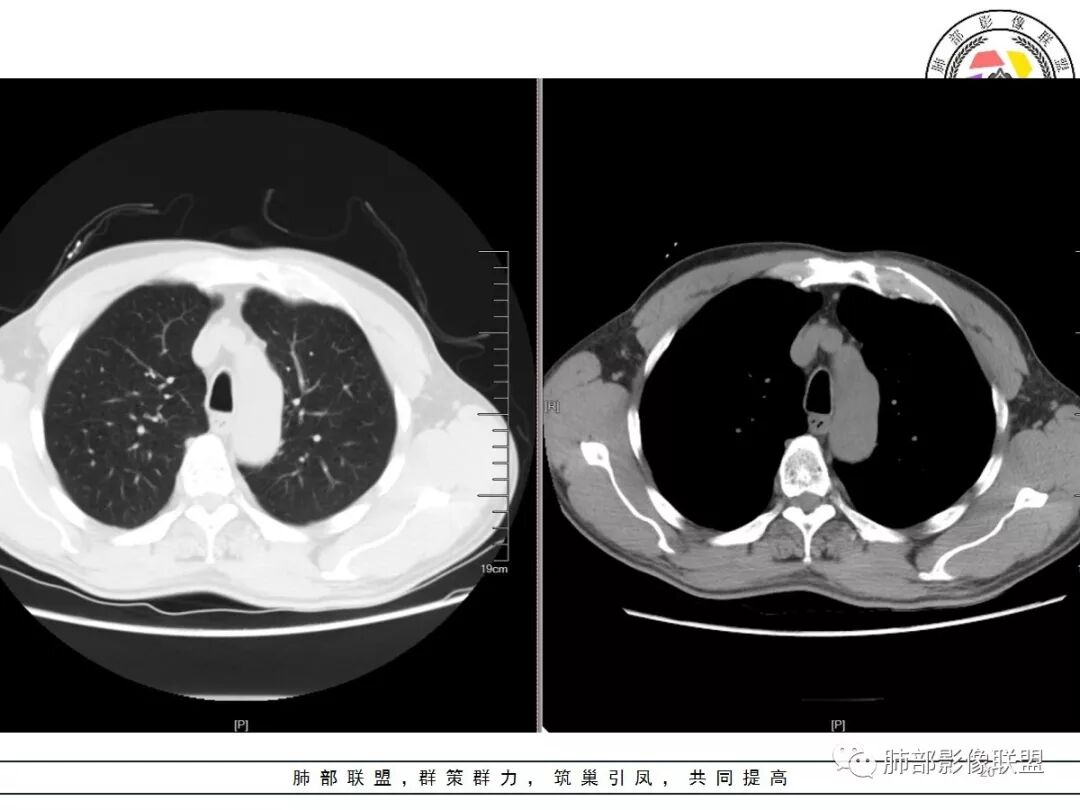

右肺结节影,边缘平直,有长索条与胸膜相连,左肺尖有条片状密度增高影,边缘清晰。左肺门斑点状钙化。考虑结核,老年人右肺上叶警惕瘢痕癌,建议复查。

右肺上叶结节灶,边缘膨隆,有毛刺,胸膜牵拉,轻度强化,左肺上叶结节灶环形强化,左肺考虑结核,右肺结节灶,不排除疤痕癌。

两肺上叶结节影,右肺结节边缘清晰,平直,有胸模牵拉,有卫星灶,强化不明显,左肺结节周边强化,两肺门淋巴结肿大,整体考虑结核。

右肺上叶结节,边缘部分膨隆,毛刺,内部有强化增粗血管影,边缘有空泡,胸膜有牵拉,考虑腺癌。鉴别结核。

右肺尖结节边缘可见分叶,结节边缘有毛刺,但左肺尖后段结节出现了典型的环形强化,考虑炎性病变,右上肺结节鉴别腺癌。还有患者食管上段壁明显增厚。

中年男性,查体发现,右肺肺上叶结节影,边缘平直收缩,周围有软毛刺,有胸膜牵拉,左肺上叶靠近纵隔不规则结节影,边缘平直内收,内有坏死。考虑良性病变可能性大,肺结核。鉴别肺癌合并结核。

中老年男性,体检发现双肺尖结节,边缘长索条,邻近胸膜粘连,病灶收缩力不太强,右肺尖病变周围少许卫星灶,增强后环形强化表现,首先考虑结核,治疗后复查

两上肺(右尖左尖后)都有小结节影,右肺尖结节边缘可见卫星灶,结节边缘平直凹陷、长毛刺,部分膨隆,增强扫描右肺尖结节强化不明确;左肺尖后段结节边缘平直凹陷,增强见环形强化。考虑结核可能性大,右上肺注意鉴别腺癌。